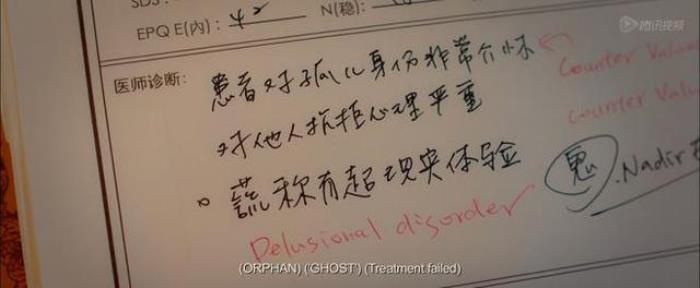

一个是心高气傲的催眠大师,一个是屡屡被鉴定治疗失败的心理疾病患者,两个人在催眠与被催眠的过程中,关于数年前的车祸案,任小妍的真实身份,治疗的真实原因,一切的谜团揭开,两个人彼此都得到了救赎。

顾洁(任小妍的真实名字)对瑞宁的催眠深度由一级直接跃入六级,从她刚踏入房间的拨钟,直接让瑞宁忘记了顾洁的真实身份——师从同门的同学。